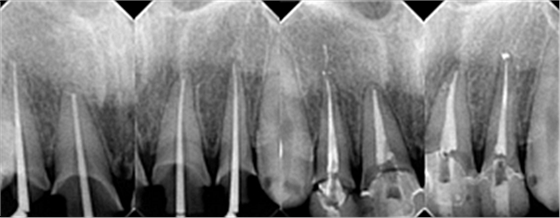

下面是醫(yī)生眼中和ct下的我們

一身病痛啊

牙結(jié)石、牙齦炎癥、牙體殘缺、慢性牙髓炎、蛀牙......

治療是從5月份開始的,醫(yī)生給我的主人驗(yàn)了血,做手術(shù)前的準(zhǔn)備,還給我們都用超聲波好好的都洗了個(gè)澡,把之前依附在我們身上的牙結(jié)石都沖了個(gè)干凈(齦上潔治術(shù))。治療先從我和其他3個(gè)兄弟開始。在麻藥的作用下,我們兄弟4個(gè)都被打開了身體,去除了已經(jīng)被蛀牙破壞的牙體,做了根管治療。

根管治療